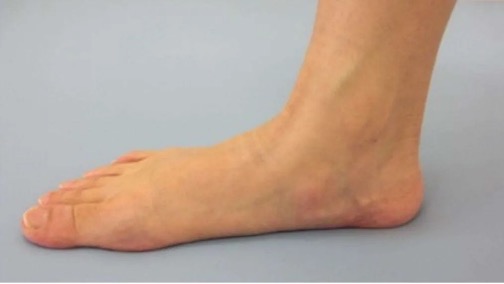

門診遇到一患者,女,15歲,學生,因“左踝及足疼痛1年余”,來我門診就診,詢問病史患者1年前出現左踝及足疼痛,行走或起步時疼痛明顯,休息后可見稍緩解。查體示雙側縱橫足弓消失,左踝及足背輕微腫脹。根據癥狀體征,診斷為“扁平足”。

扁平足,顧名思義,是指足弓扁平或消失,這是一種常見的足部畸形。其主要癥狀包括腳內側緣痛或后跟痛,走遠路乏力等。然而,扁平足的危害遠不止于此。它可能導致運動受限,甚至引起足部其他關節以及踝關節、膝關節、髖關節的連鎖反應,如發生炎癥、變形等。這些連鎖反應不僅會增加患者的疼痛感,還可能影響正常的行走和站立姿勢,嚴重時甚至可能影響日常生活。

扁平足的檢測方法主要有兩種:足印法和影像學檢查。足印法簡單易行,通過觀察足印最窄區與足長的比例,可以初步判斷是否存在扁平足。影像學檢查則更為精確,通過足部X線檢查,可以測量足弓角度,明確足弓結構,從而準確判斷是否存在扁平足。